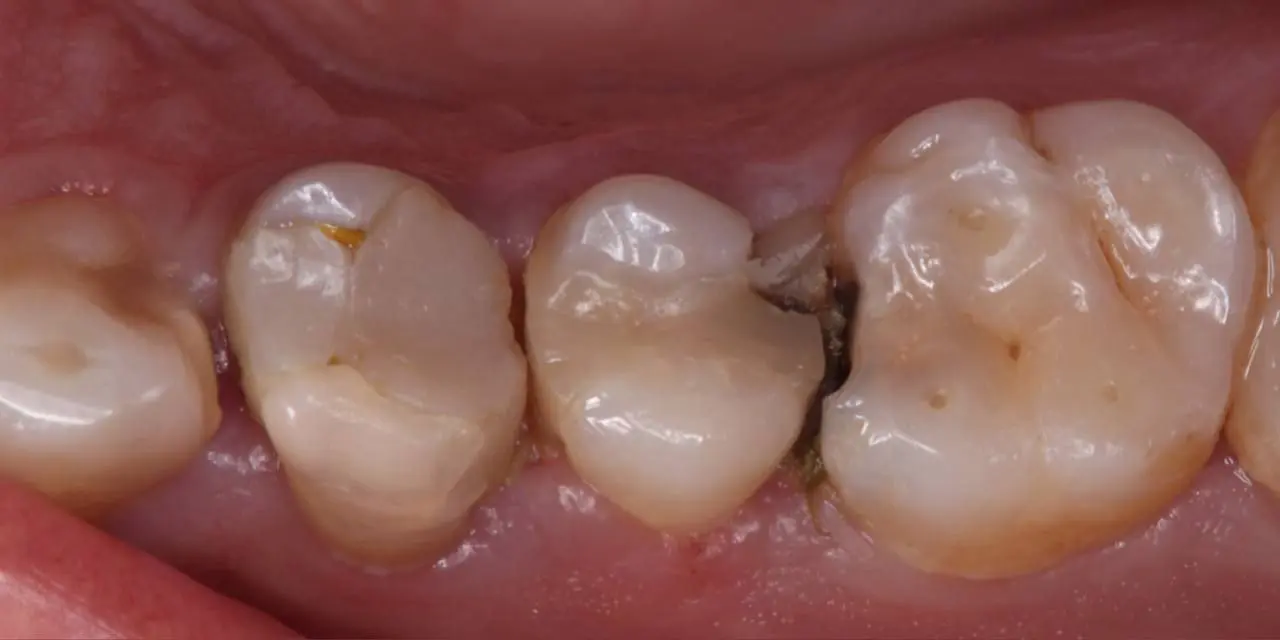

قبل

بعد